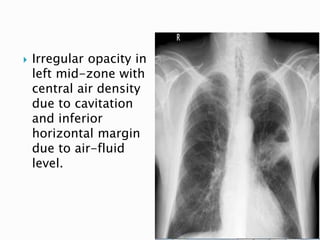

 Irregular opacity in

left mid-zone with

central air density

due to cavitation

and inferior

horizontal margin

due to air-fluid

level.